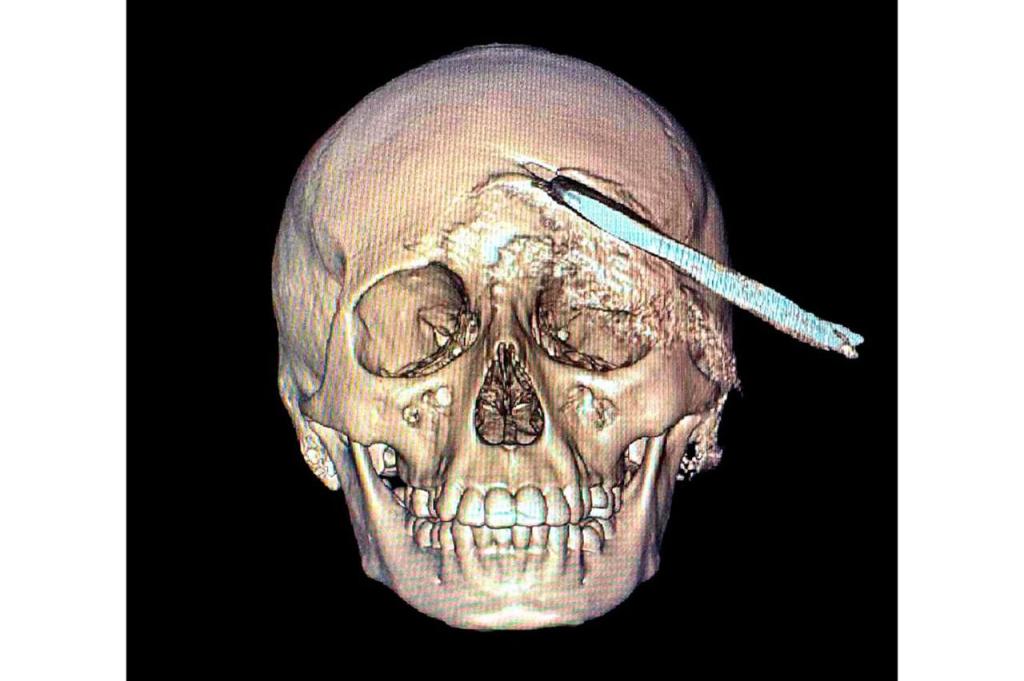

El Instituto Mexicano del Seguro Social (IMSS) en Yucatán logró un hecho médico sin precedentes al retirar, mediante una compleja cirugía, una herramienta agrícola -coa- de aproximadamente 30 centímetros incrustada en el cráneo de un adolescente de 15 años, procedimiento que permitió salvarle la vida.

El 2 de noviembre, Yael fue trasladado desde el municipio de Acanceh al Hospital General Regional (HGR) No. 12 del IMSS en Mérida, donde la directora, doctora Claudia González Ramírez, y un equipo de especialistas ya se encontraban preparados para recibirlo y atender la emergencia. Tras confirmarse un traumatismo craneoencefálico severo, se realizaron estudios

inmediatos que determinaron la profundidad y ubicación del objeto.

Los estudios de imagen permitieron ubicar con precisión el objeto, mientras que el menor recibía tratamiento con antibióticos de amplio espectro para prevenir infecciones asociadas con el instrumento metálico.

Después de un análisis minucioso y una planeación quirúrgica, el doctor Ornelas González dirigió un procedimiento de cuatro horas que permitió retirar exitosamente el machete curvo sin afectar tejido cerebral, en una intervención que confirmó la pericia y capacidad del equipo médico.